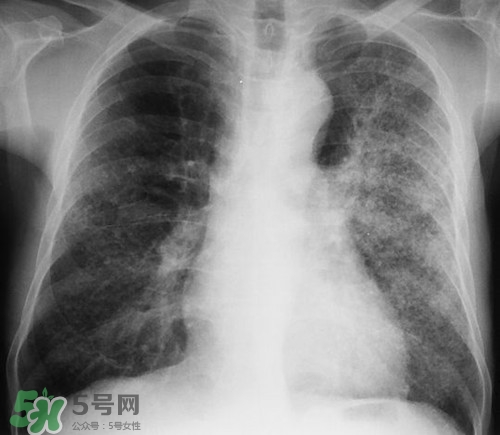

肺炎是常見的呼吸道感染疾病,這病也確實(shí)麻煩,如果處理不當(dāng)可能危及生命哦,那么肺炎會不會傳染呢?吃什么好的快呢?下面我們來介紹下吧!